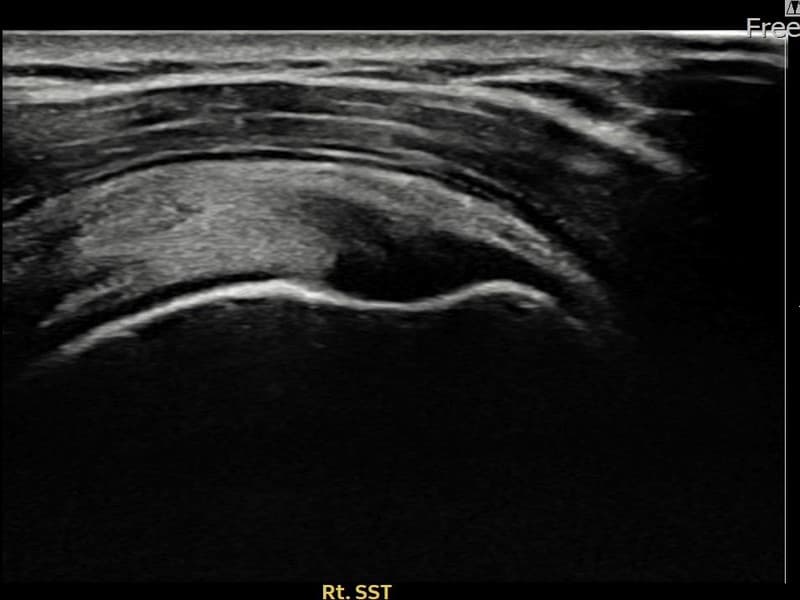

术前

术前超声确认右侧 冈上肌腱 附着部部分撕裂,右侧冈上肌腱回声不连续伴肌腱缺损(10mm × 4mm (肌腱厚度约42%缺损))。术后超声显示撕裂部位充满再生组织,肌腱连续性恢复,回声模式正常化。